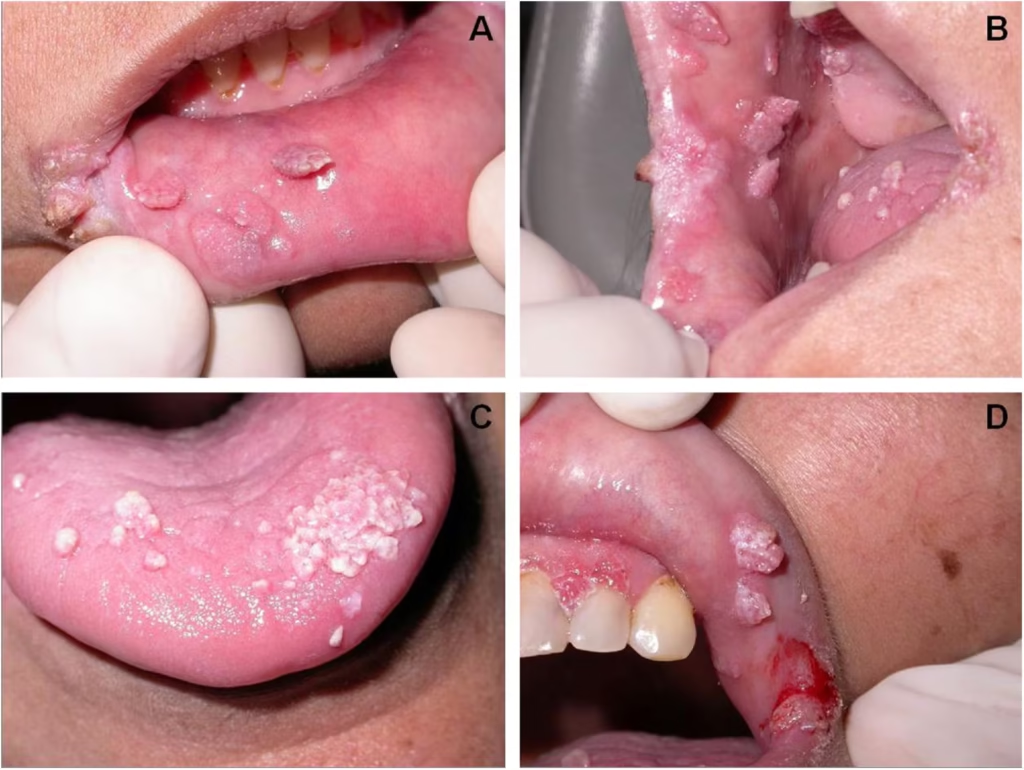

این ویروس از طریق تماس مستقیم پوست یا مخاط، مانند بوسیدن، رابطه جنسی دهانی یا تماس نزدیک منتقل میشود. اکثر افراد مبتلا به HPV دهانی هیچ علامتی ندارند و خودشان هم نمیدانند که ویروس را دارند و میتوانند موجب سرایت ویروس به شریک جنسی خود بشوند . این ویروس بیش از 200 نوع مختلف دارد که میتوانند باعث ایجاد ضایعات گلکلمیشکل کوچک روی پوست، ناحیۀ تناسلی و دهان بشوند. ابتلا به این ویروس در بسیاری از مواقع هیچ علامتی ندارد و در افراد با سلامت جسمی خوب، بدون درمان، طی ۱-۲ سال از بدن پاک میشود؛ اما برخی اوقات سیستم ایمنی بدن قادر به حذف ویروس نبوده و برای سالها میتواند در بدن به شکل نهفته باقی بماند. دقیقا مشخص نیست که چرا این ویروس در برخی افراد به راحتی از بدن حذف شده و در برخی دیگر شکل مزمن پیدا میکند اما احتمالا این امر مرتبط با کارآمدی سیستم ایمنی فرد و یا نوع ویروس HPV است. در صورت وجود ضایعات پوستی مخاطی، این ضایعات خود به خود برطرف نمیشوند و حذف آنها نیاز به مداخلات درمانی دارد. این ضایعات منبع انتقال عفونتاند و تماس با آنها میتواند منجر به سرایت ویروس به افراد دیگر شود. برخی سویههای این ویروس، بهویژه انواع 16، 18، 31 و 33 با افزایش ریسک ابتلا به سرطانهای گردن رحم و ناحیۀ حلق و خلف دهان مرتبطاند؛ به عبارت دیگر، در افراد مبتلا به این سویههای ویروس پاپیلومای انسانی احتمال ابتلا به سرطانهای دهان و رحم بیشتر از افرادی است که به این ویروس مبتلا نیستند.

علائم زگیل دهانی

Symptoms of oral warts

برخی اوقات نماهای نرمال دهان مثل جوانه های چشایی زبان با ضایعات اچ پی وی دهانی اشتباه گرفته میشوند. برای تشخیص و اطمینان از ابتلا به اچ پی وی دهانی بهترین گزینه مراجعه به متخصص بیماری های دهان است.

معاینۀ کامل دهان توسط متخصص بیماریهای دهان انجام میشود. درصورت مشاهدۀ ضایعه، برداشت ضایعه توسط لیزر و در برخی مواقع، توسط برش با تیغ و بخیه انجام میشود. ضایعه برای تعیین سروتایپ (نوع ویروس) و همچنین، تشخیص قطعی به پاتولوژی فرستاده میشود. درصورتیکه ضایعه مرتبط با سویههایی با ریسک بالا برای ایجاد سرطانهای دهان (انواع 16 و 18) باشد، بررسی دورهای منظم به بیماران توصیه میشود.

15. روشهای شایع برداشت زگیل دهانی چیست؟

روشهای رایج برداشتن زگیل دهانی شامل موارد زیر است:

1. جراحی برداشتن (Excision): ضایعه با تیغ جراحی برداشته میشود. این روش معمولاً برای زگیلهای بزرگ یا مقاوم استفاده میشود.

2. لیزر درمانی: با استفاده از لیزر، بافت زگیل تخریب میشود. این روش دقت بالایی دارد و خونریزی کمی ایجاد میکند.